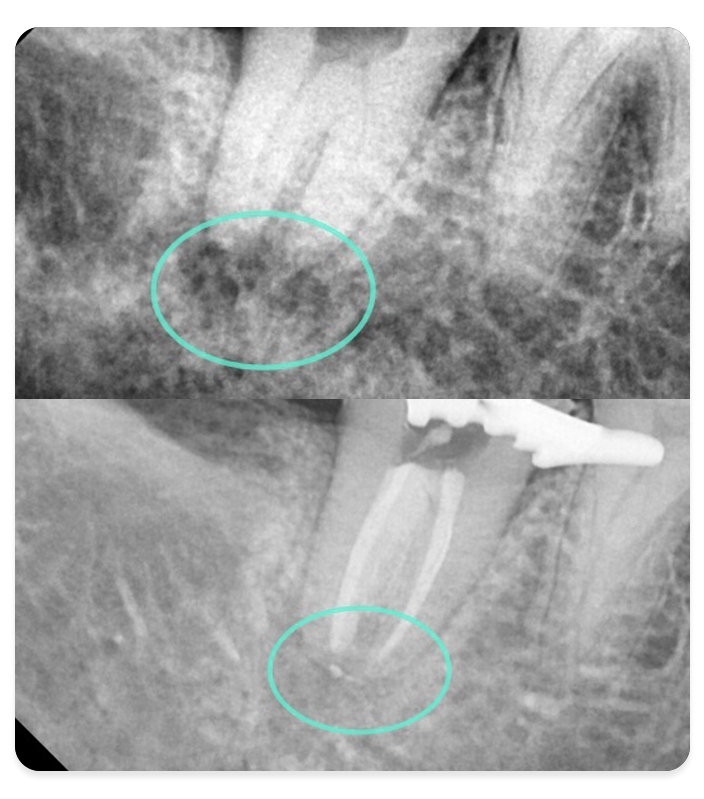

이전에 신경치료를 받았음에도 불구하고 증상이 지속되거나 재발한 경우,

문제의 원인을 철저히 분석하고 치료 가능성을 평가하여

다시 건강한 상태를 찾을 수 있도록 돕는 치료입니다.

신경치료 실패 원인 및 기존 근관 충전 상태 등을 면밀히 분석

정확한 진단을 통해 재치료의 성공 가능성을 평가하고 치료 계획 수립

이전에 해결되지 못했던 염증이나 근관 형태의 문제를 해결하는 데 중점

방사선·근관 진단

정밀한 영상 진단으로 근관 상태 파악